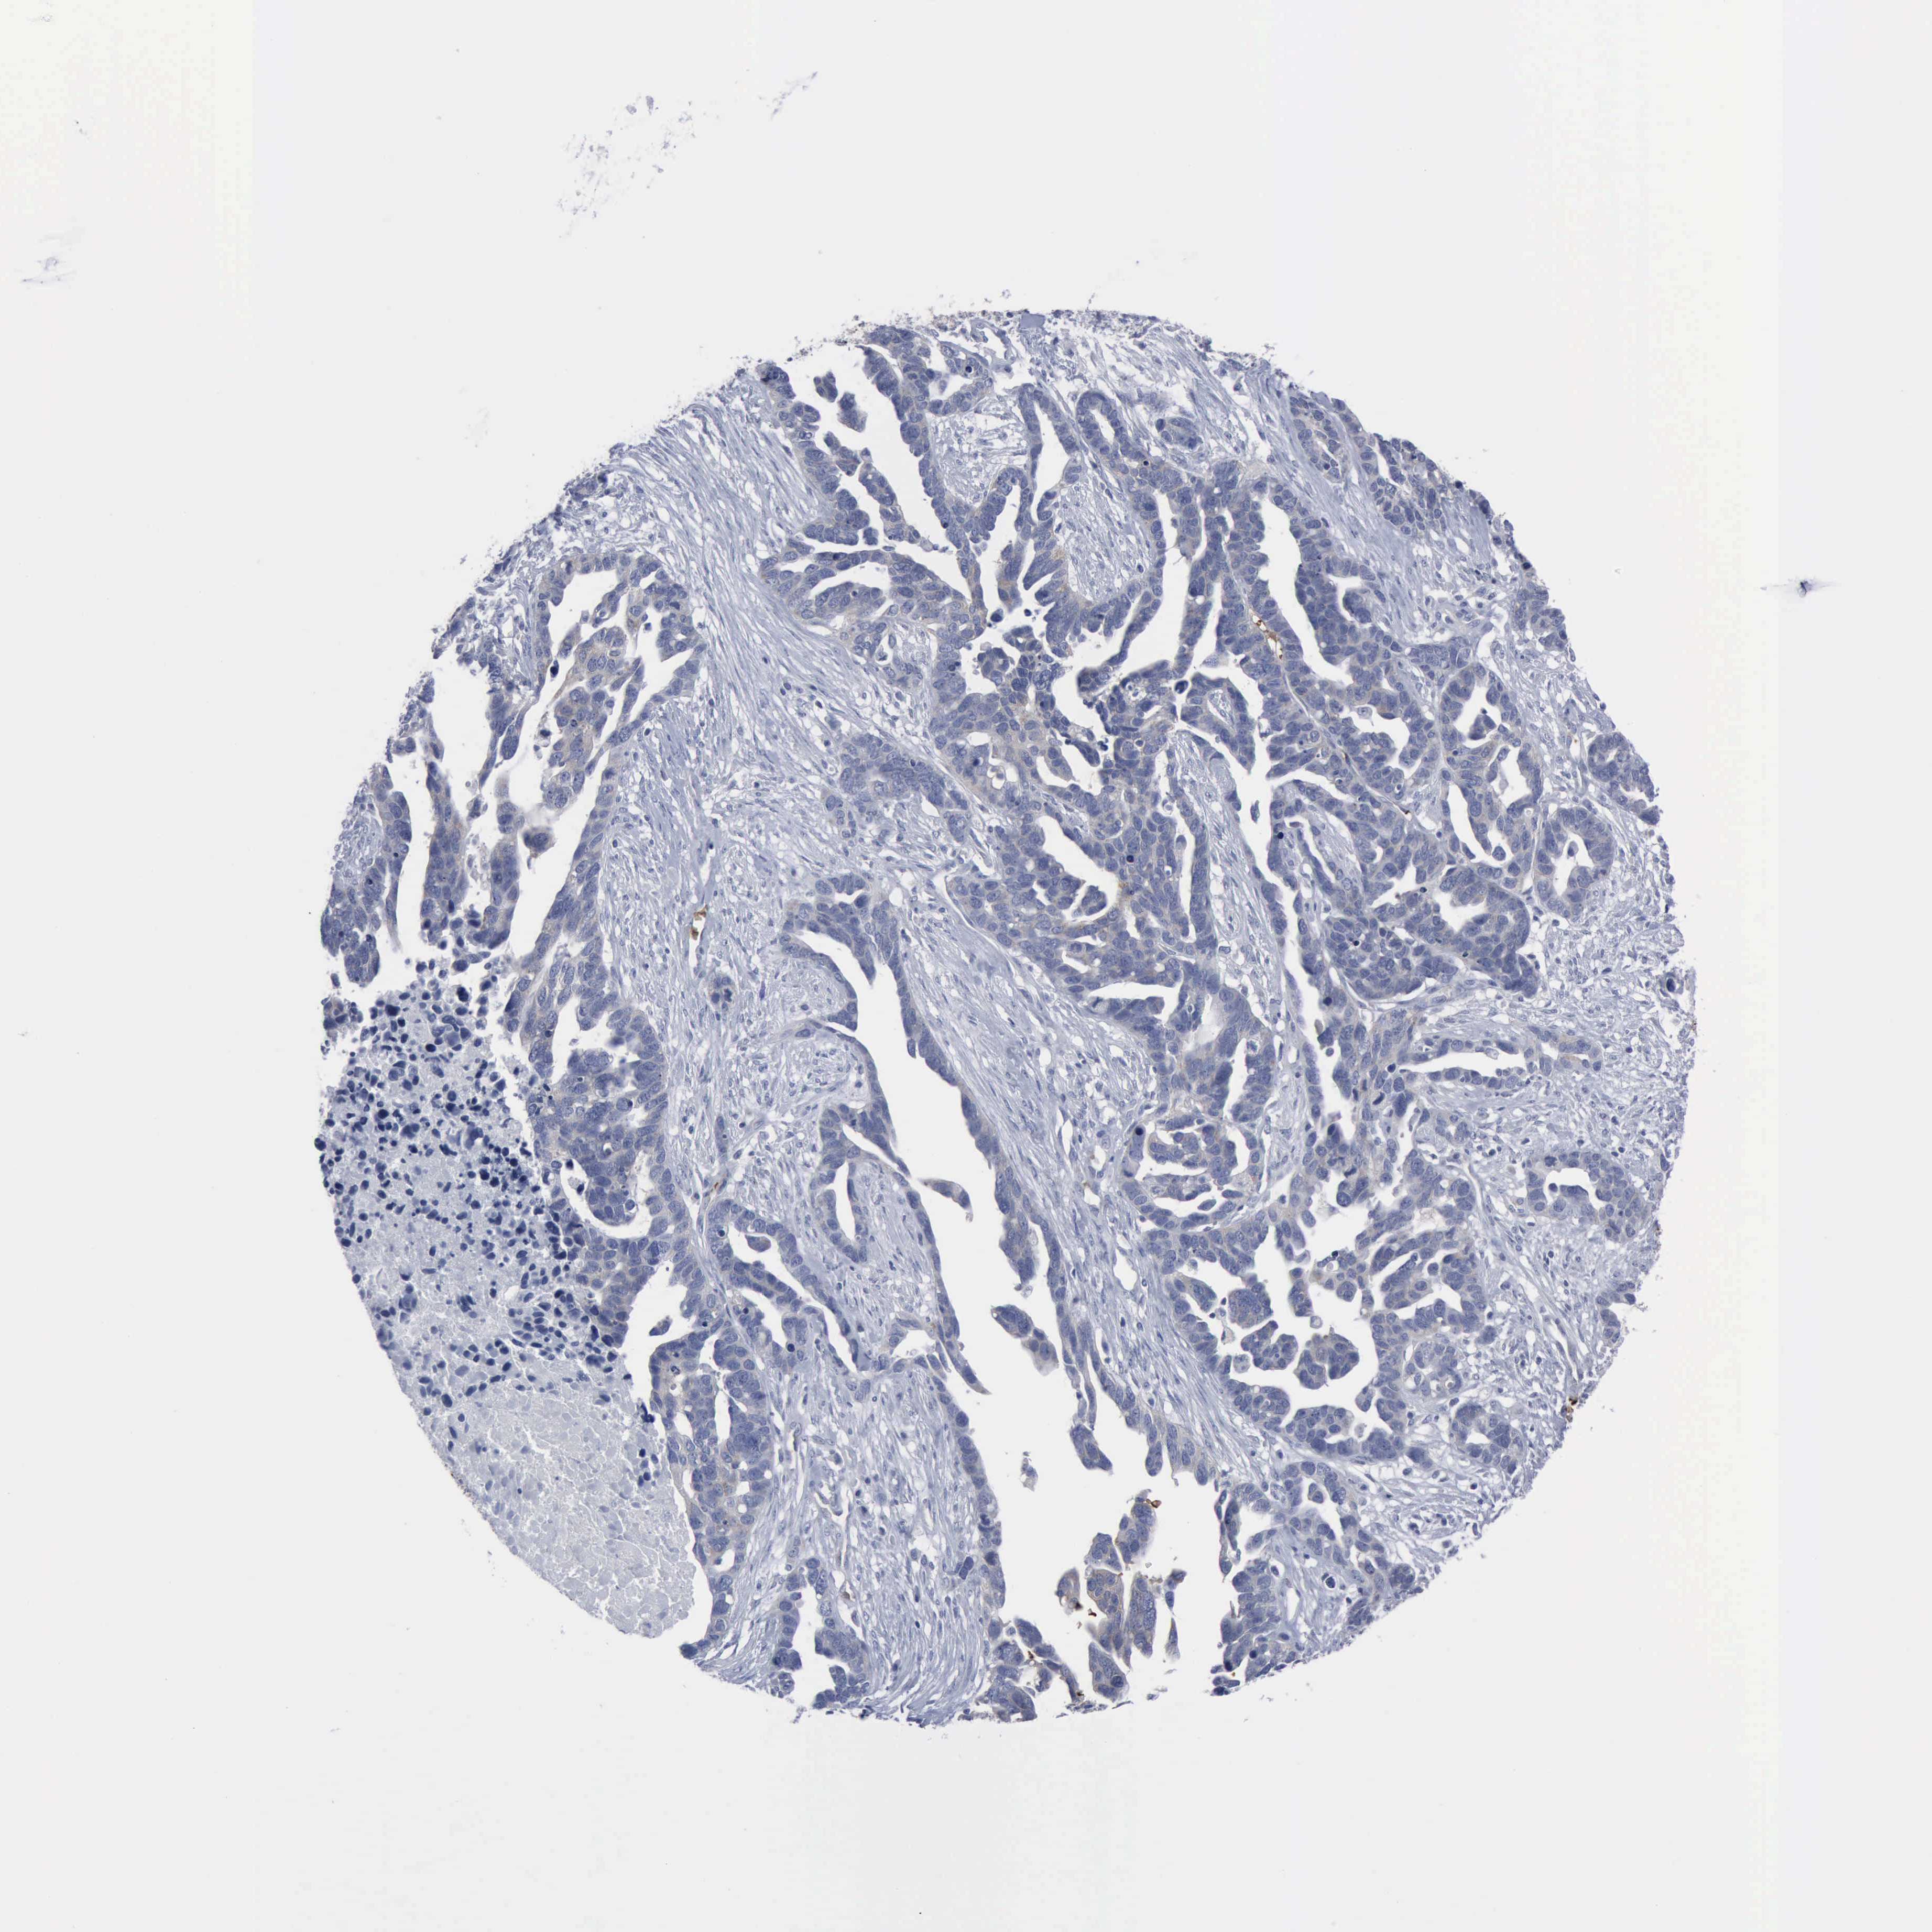

OVARIAN CANCER - Protein expressioni

A mouse-over function shows sample information and annotation data. Click on an image to view it in a full screen mode. Samples can be filtered based on level of antibody staining by selecting one or several of the following categories: high, medium, low and not detected. The assay and annotation is described here.

Note that samples used for immunohistochemistry by the Human Protein Atlas do not correspond to samples in the TCGA dataset.

Antibody stainingi

Antibody staining in the annotated cell types in the current human tissue is reported as not detected, low, medium, or high, based on conventional immunohistochemistry profiling in selected tissues. This score is based on the combination of the staining intensity and fraction of stained cells.

Each image is clickable and will lead to virtual microscopy that enables deeper exploration of all samples and also displays staining intensity scores, fraction scores and subcellular localization as well as patient and tissue information for each sample.

Antibody CAB000361

Staining

High

Medium

Low

Not detected

Intensity

Strong

Moderate

Weak

Negative

Quantity

>75%

75%-25%

<25%

None

Location

Nuclear

Cytoplasmic/membranous

Cytoplasmic/membranous,nuclear

Cystadenocarcinoma, mucinous, NOS

Carcinoma, endometroid

Cystadenocarcinoma, serous, NOS